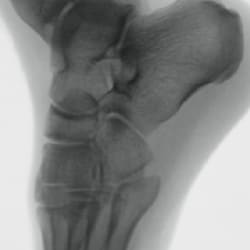

Metal correction

Minimizing halation for clear visualization in orthopedic procedures with bolts and implants.

No metal correction